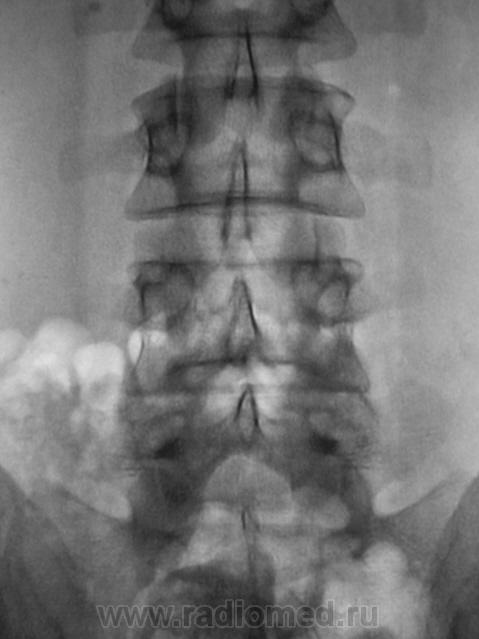

Пациент с болями в пояснице, направлен на рентгенологическое исследование поясничного отдела позвоночника.

А позвонков разве не 6? И подготовить бы больного. У нас в поликлинике, почемуто не принято готовить больных к съёмке ПКОП,  только если к ЭУ.

Ничего, Вы себе не нафантазировали, Игорь Иванович. В данном случае "двуконтурности" заднего края отдельных позвонков не избежать, так как на рентгенограмме в прямой стандартной проекции (снимок выполнен стоя), вроде-бы, как-бы намечается некоторое искривление позвоночника во фронтальной плоскости. Конечно, это никакое не искривление, это просто ротация - 1 - 2 позвонков, и становится понятным, что если 1-2 позвонка чуть ротировались, то на ровность заднего контура всех поясничных позвонков расчитывать не приходится.

О ротации, также свидетельствует различная длина поперечных отростков одноименного позвонка, и это видно.

И еще один вопрос... Как расценивать "вдавленность" контура замыкательной пластинки Л5 - желтые стрелки, но с учетом красных стрелок.

А не "дефектна - ли" дужка Л5?

Вроде складывается впечатление о спондилолизе.

Похоже, и весьма.